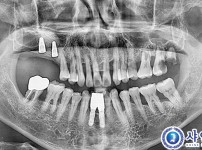

상악동거상술 임플란트 9개 - 오스템칼슘

해당 게시물은 의료법 제56조에 의거하여 로그인 후 열람이 가능합니다.

구분 임플란트